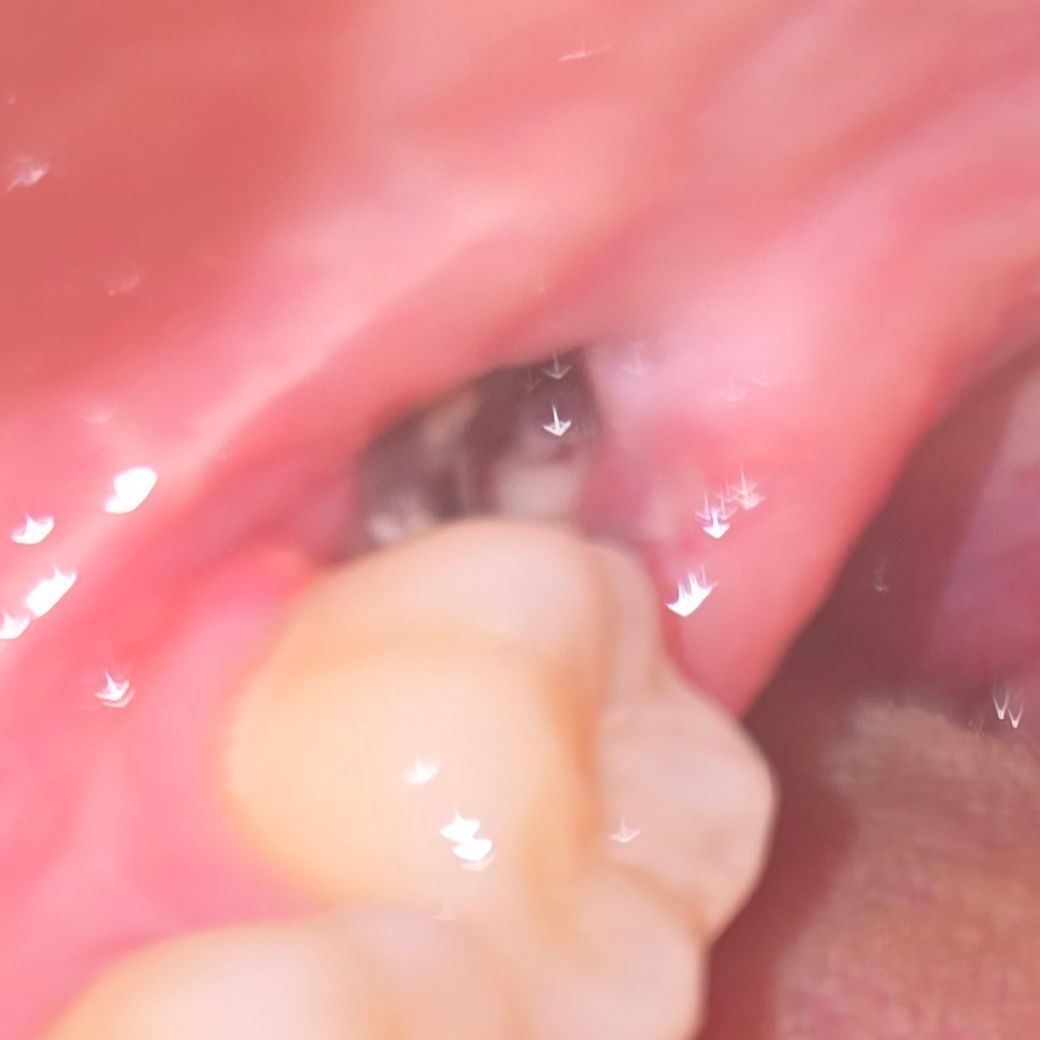

매복사랑니 발치 4일차) 드라이소켓 가능성 있을까요..? (발치부위 사진 주의)

안녕하세요, 발치한지 4일차(어제)에 고여있던 피떡이 사라지더니 5일차(오늘)부터 저런 하얀부분들이 군데군데 보이기 시작하더라고요...

발치 첫날부터 지금까지 통증도 거의 없었고...지금도 드문드문 비릿한 맛이 나는거 외엔 특이사항은 없는데.... 구멍이 뚫린 뒤로 너무 불안하더라고요...ㅜㅜ 침을 너무 세게 삼켜서 그런거아닌지 싶기도 하고...ㅠ치과 방문하려면 주말까지 기다려야돼서 도움받을 수 있을까하여 질문 드립니다ㅠㅠ

• 2번 째 사진

원래 사랑니 뽑은 후에 정상적으로 아무는 과정에서 구멍이 생깁니다. 하얗게 보이는 것은 잇몸 딱지 앉은 것으로 보면 되고 그냥두면 됩니다. 굳이 치과에 안가도 됩니다.

지금 사진에 보이는 것으로는 드라이소켓으로 보이지는 않습니다. 크게 문제는 없어보입니다

치유 과정 중에 나타나는 염증, 육아조직 반응으로 보입니다. 특별히 치유부전이나 드라이소켓의 양상은 아닙니다. 더군다나 통증이 심하지 않다면 괜찮습니다.